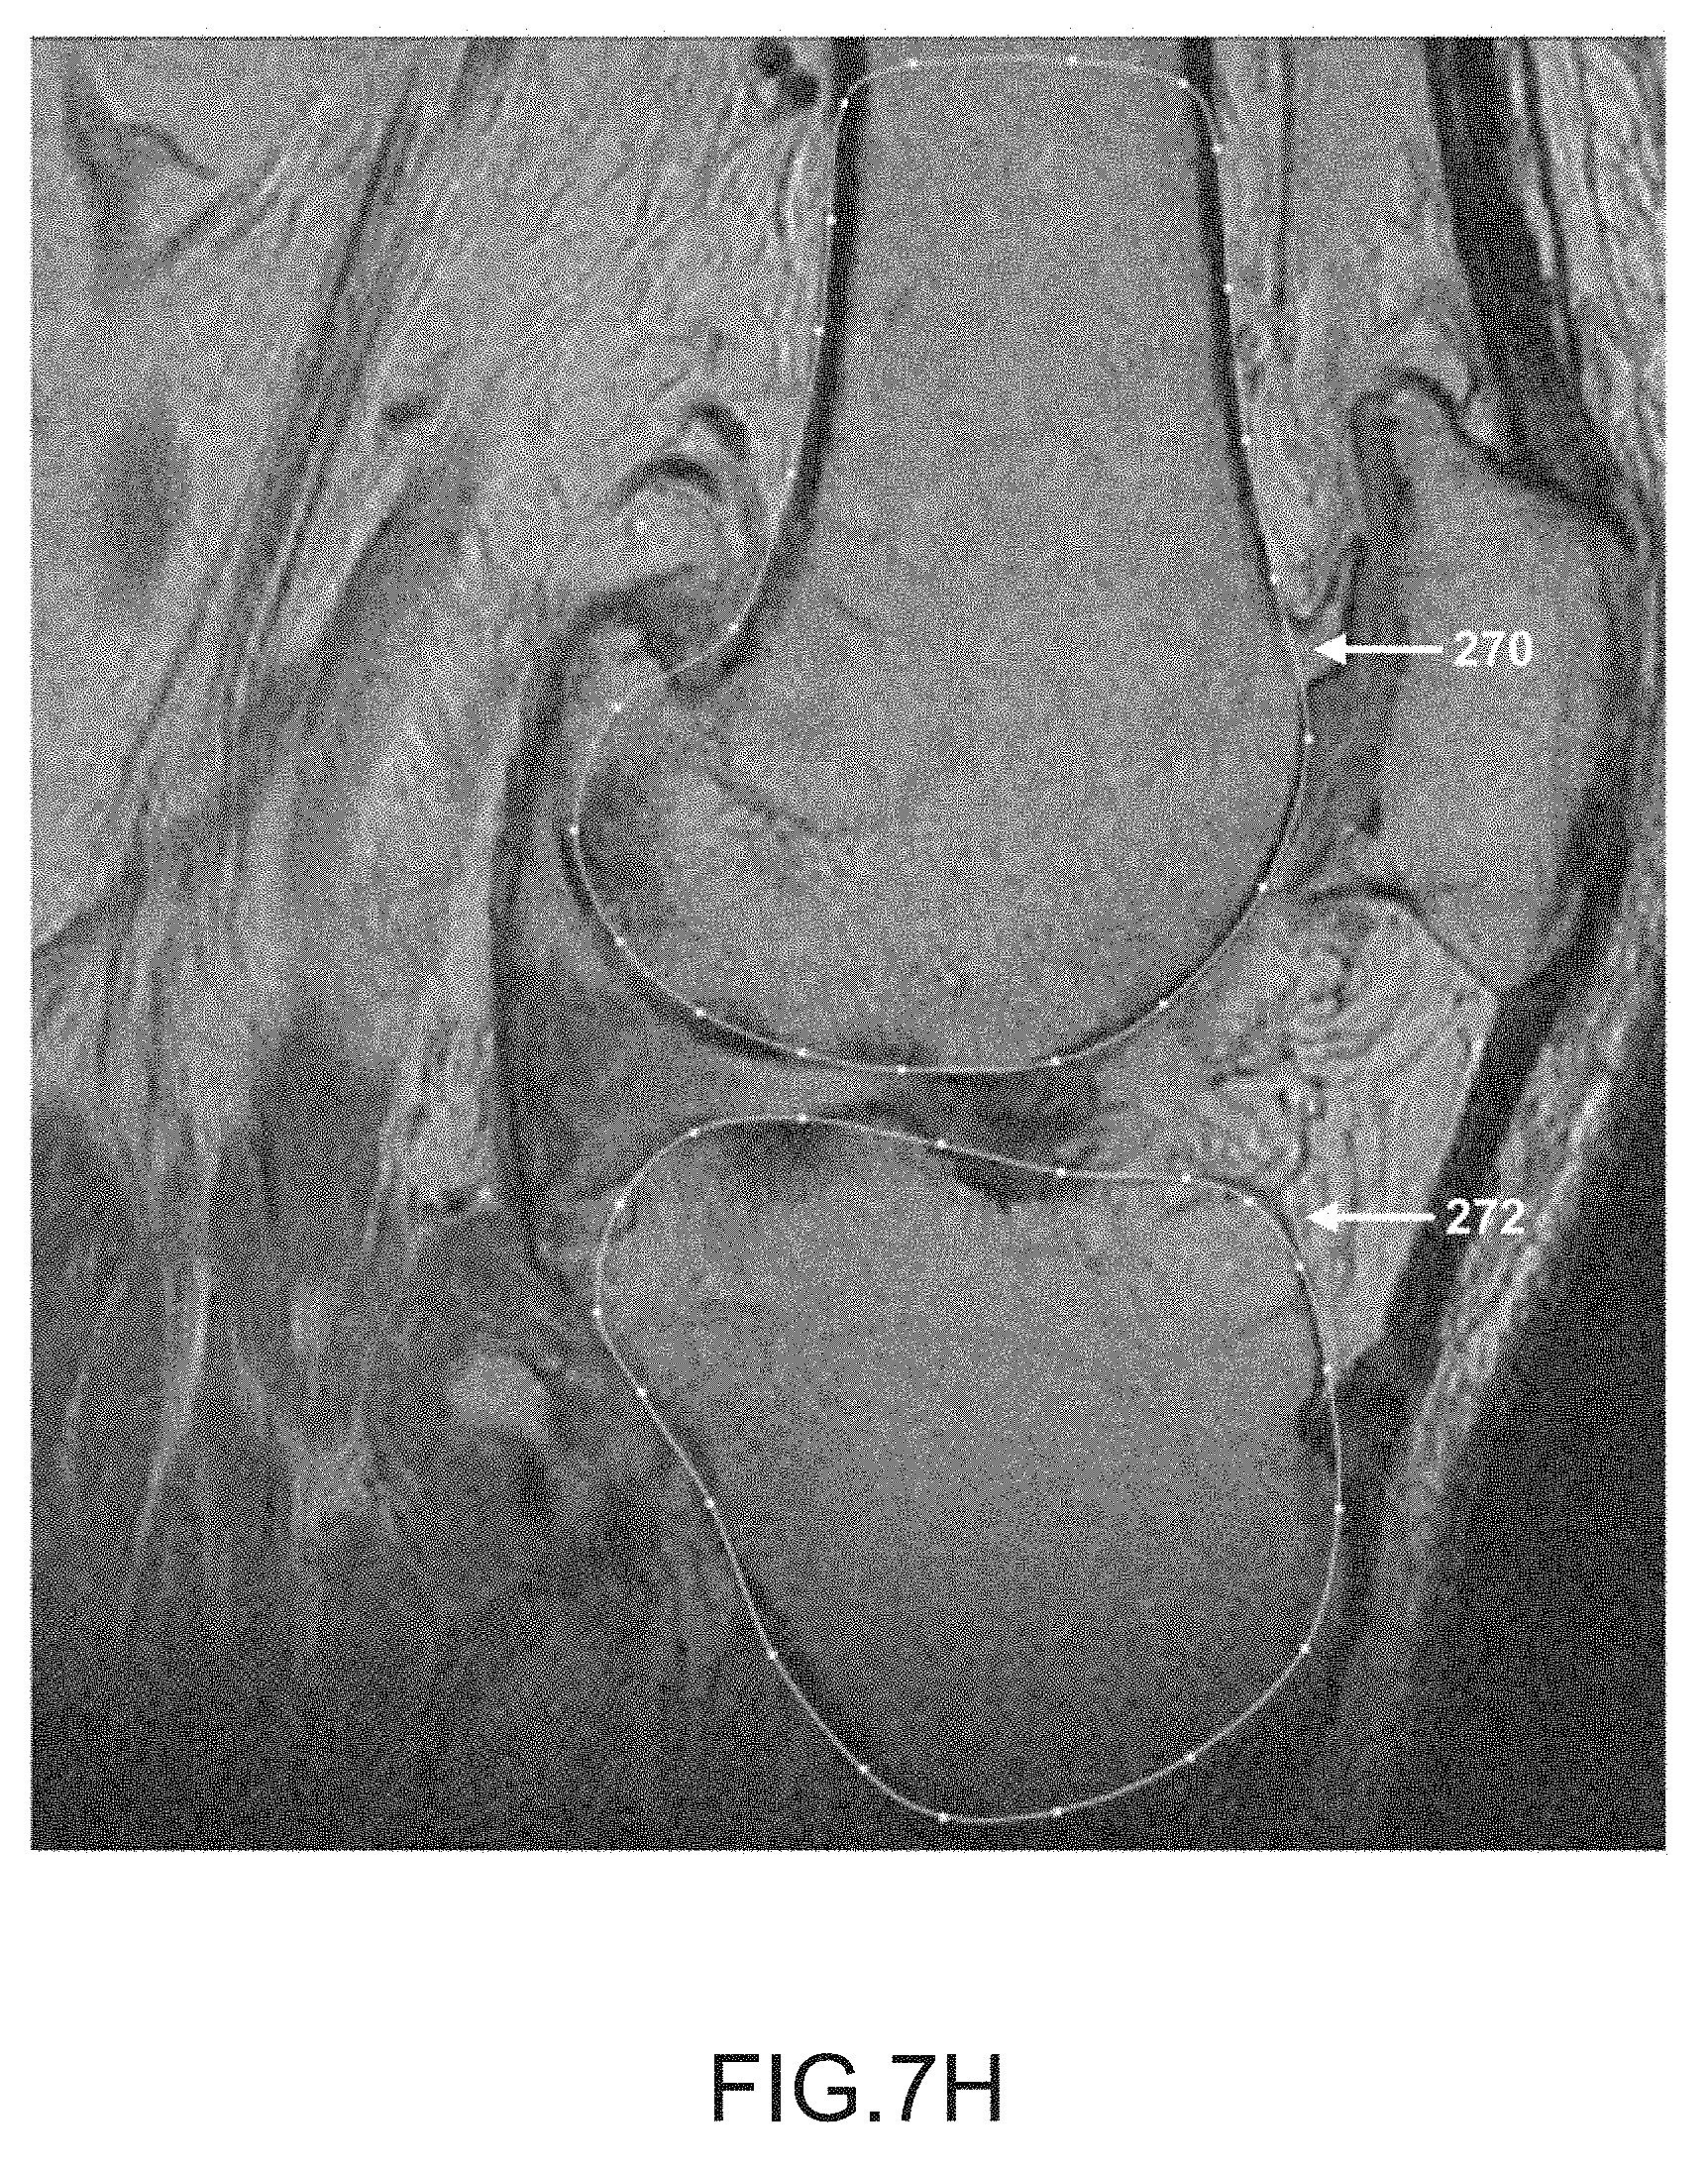

FIG. 7H is another sagittal plane image slice of a segmented femur and tibia.

After operation 250 obtains scan data (e.g., scan images 16) generated by imager 8, operation 252 may be performed to segment the femur data of the scan data. During this operation, the femur may be located and spline curves 270 may be generated to outline the femur shape or contour lines in the scan slices, as depicted in FIGS. 7A-7K. It should be appreciated that one or more spline curves may be generated in each slice to outline the femur contour depending on the shape and curvature of the femur as well as the femur orientation relative to the slice direction.

[0165]

After operation 256, operation 258 may be performed to segment the tibia data in the scan data. During this operation, the tibia is located and spline curves may be generated to locate and outline the shape of the tibia found in the scan slices, as depicted by tibia spline curves 272 in FIGS. 7A-7K. It should be appreciated that one or more spline curves may be generated in each slice to outline the tibia depending on the shape and curvature of the tibia as well as the tibia orientation relative to the slice direction.